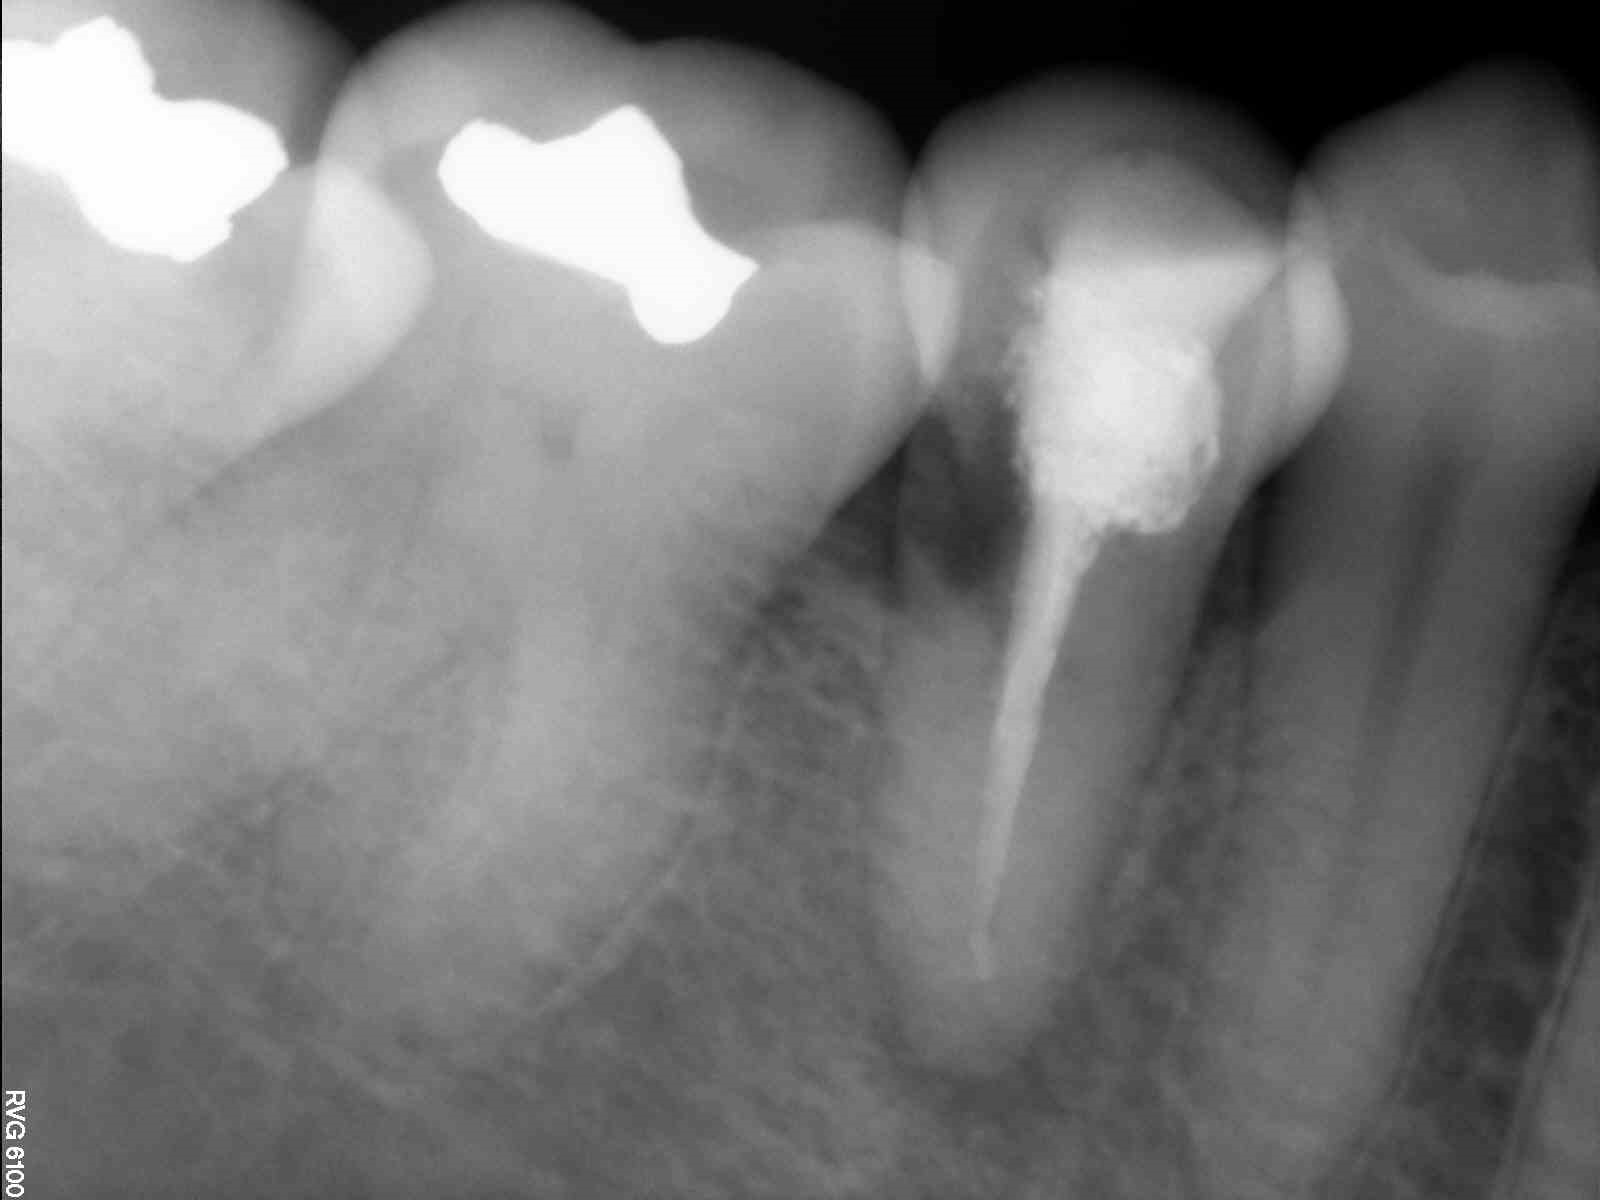

Fig. 1: Panoramic radiograph of the initial situation. (All images: Dr Johnny Onori)

The radiographic examination showed periapical radiolucency and a radiolucent lesion in the cervical area of the tooth (Figs. 1 & 2). To determine the extent and depth of the lesion, a CBCT scan was performed (Fig. 3). Based on the CBCT images and 3D reconstructions, a diagnosis of Heithersay Class III external cervical invasive root resorption (ECIR) was determined in an endodontically treated tooth with symptomatic periapical periodontitis. The patient was informed of the diagnosis, treatment plan alternatives and prognosis of the case.